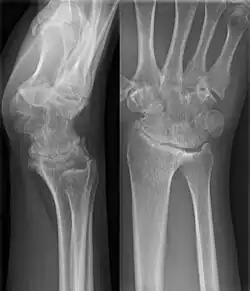

Karpale Koalition

Eine karpale Koalition ist eine feste Verbindung zwischen Handwurzelknochen, die normalerweise über ein Gelenk in Kontakt stehen. Dabei kann diese Verbindung knöchern (Synostose), knorpelig (Synchondrose) oder bindegewebig (Syndesmose) ausgebildet sein. Als Ursache wird von einer mangelhaften Differenzierung der Handwurzelknochen zwischen der 4. und 8. Embryonalwoche ausgegangen[1].

Wenn eine karpale Koalition isoliert auftritt, was der häufigere Fall ist, sind in der Regel zwei Knochen der gleichen Handwurzelreihe betroffen, beim Auftreten im Rahmen von Syndromen oder anderen globaleren Störungen treten auch Verbindungen von mehreren Knochen beider Reihen auf[1][5]. Die bei Weitem am häufigsten verschmolzenen Knochen der Handwurzel sind Os lunatum und Os triquetrum gefolgt vom Os hamatum mit dem Os capitatum[1].

Eine Verschmelzung der Handwurzelknochen kann auch sekundär bei entzündlichen Erkrankungen wie z. B. der juvenilen idiopathischen Arthritis auftreten.